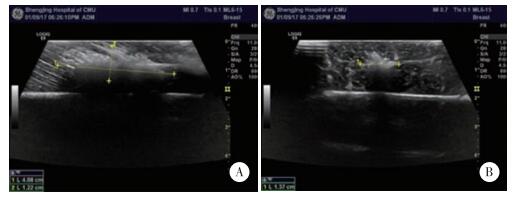

2 结果 2.1 超声观察随着RFA的进行,超声图像可见逐渐扩大的高回声气化区,待消融结束后,观察气化区边界欠清晰,质地较均匀,数秒后气化区边界不明显,与未消融部位回声相近(图 1)。

| A,long and short diameters of gasification volumes following radiofrequency ablation at 45 W for 60 s in muscle;B,maximum diameter of gasification volume following ablation at 45 W for 60 s in muscle. 图 1 RFA的超声图像 Fig.1 Ultrasound images following RFA |